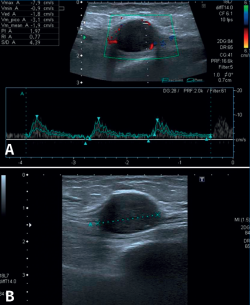

Una reciente analítica convencional de sangre y orina fue normal. Las radiografías del tobillo, aportadas también por la enferma, eran normales. Con el diagnóstico de sospecha de STT por algún tipo de masa se decide la realización de una ecografía del tobillo derecho. El informe del radiólogo informó de una lesión hipoecoica y homogénea, sólida y moderadamente vascularizada (predominantemente en la zona periférica) de aproximadamente 2 × 1,8 cm en el eje transversal y longitudinal. La lesión depende del NTP al nivel del túnel del tarso, siendo dolorosa a la palpación ecográfica. Las imágenes representativas de este estudio las podemos ver en la Figura 1.

Figura 1. Ecografía de tobillo. A: vista de eje largo del nervio tibial posterior que muestra masa de partes blandas con vascularización en la ecografía Doppler color; B: imagen que muestra el tumor del nervio tibial posterior como una masa de tejido blando hipoecoico, con refuerzo posterior dentro de la vaina del nervio.

Una vez tenemos el diagnóstico de presunción, debemos apoyarnos en pruebas de imagen para llegar el diagnóstico de certeza. Nosotros pensamos que el algoritmo que debemos seguir es el siguiente. En primer lugar, solicitar una radiografía simple de tobillo para descartar cualquier afectación o anomalía ósea. Dado que nos encontramos ante un paciente con clínica de atrapamiento compresivo nervioso, pensamos que es muy costo-eficiente realizar una prueba de ultrasonido musculoesquelética que nos informe grosso modo de la causa que está provocando la dolencia de nuestro enfermo. La ecografía mostrará típicamente una masa homogénea hipoecoica, ovoide, sólida, vascularizada en su periferia y delineada con precisión en la periferia del nervio(23,24) que, en manos de un ecografista experimentado, prácticamente nos daría el diagnóstico.